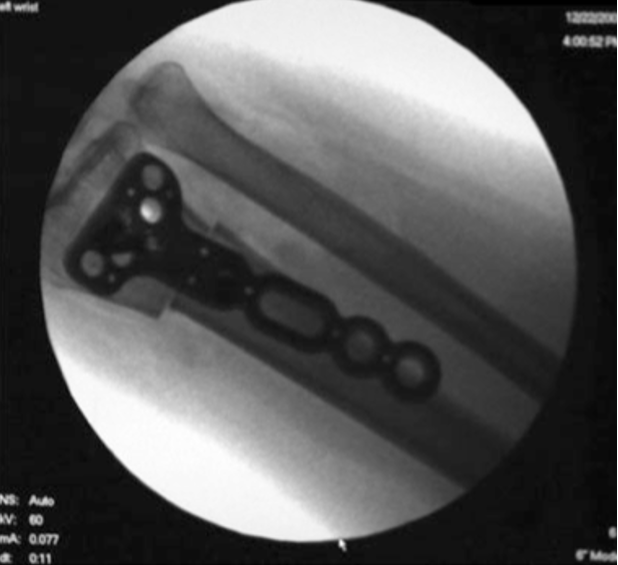

• Opções cirurgicas para descomprimir o semilunar (3)?

A

• Encurtamento do rádio (mais realizado na prática)

• Alongamento da ulna → pode complicar com PSA

• Encurtamento do capitato (em casos de ulna neutra)